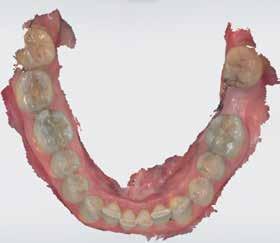

72 FDC 2026 Speaker: Full Arch Implant Reconstruction in the Digital Era: Past, Present and Future